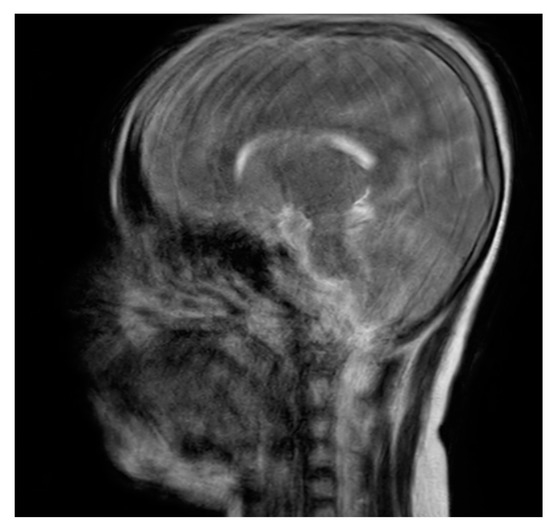

Motion blurriness happens due to patient motion, swallowing, and even breathing in the case of the head and neck region. The degree of blurriness could fall into a range of minimal to extensive blur. A pediatric MRI image with severe motion blurs and distortion of the image is presented in the sagittal section (Figure 8). This kind of artifact requires a re-scan.

Figure 8. MRI image of a pediatric patient taken for neuroimaging purposes. Severe motion blurs and distortion of the image are evident.